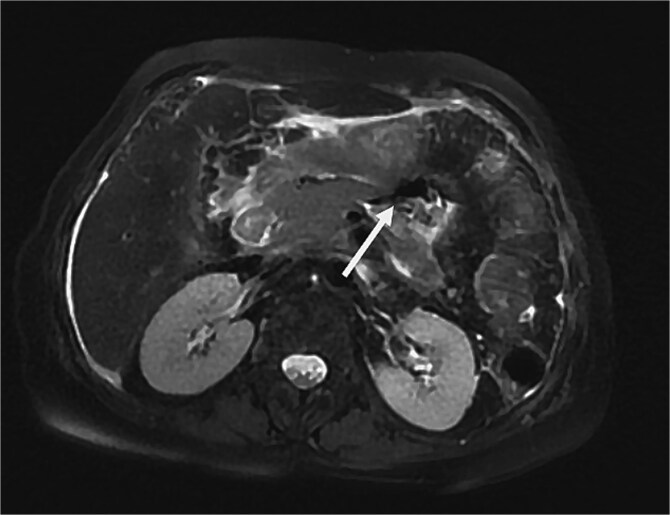

胰管断裂综合征(DPDS)是一种罕见的疾病,其特征是胰管断裂,使活的胰腺组织与胃肠道分离。它常伴随急性或慢性胰腺炎、腹部创伤或胰腺手术,导致导管坏死或解体。DPDS提出了重大的诊断和管理挑战,特别是在延迟发病的病例中。作者报告了一个坏死性胰腺炎后复发性胰液收集的复杂病例,强调了延迟DPDS表现的可能性。先进的成像技术,包括内窥镜超声检查,对比增强CT和MRCP,用于诊断。由于保守治疗失败,我们进行了远端胰腺切除术,解决了这个问题,并防止了感染、败血症或胰瘘等并发症。该病例强调了早期识别DPDS在影像学上的重要性,有助于及时治疗并降低长期并发症的风险。

Disconnected pancreatic duct syndrome (DPDS) is a rare condition characterized by a disruption of the pancreatic duct, separating viable pancreatic tissue from the gastrointestinal tract. It often follows acute or chronic pancreatitis, abdominal trauma, or pancreatic surgery, leading to ductal necrosis or disintegration. DPDS presents significant diagnostic and management challenges, especially in cases with delayed onset. The authors report a complex case of recurrent pancreatic fluid collections after necrotizing pancreatitis, highlighting the potential for delayed DPDS manifestation. Advanced imaging techniques, including endoscopic ultrasonography, contrast-enhanced CT, and MRCP, were used for diagnosis. Due to failure of conservative treatment, a distal pancreatectomy was performed, resolving the issue and preventing complications such as infection, sepsis, or pancreatic fistula. This case underscores the importance of early recognition of DPDS on imaging, facilitating timely treatment and reducing the risk of long-term complications.